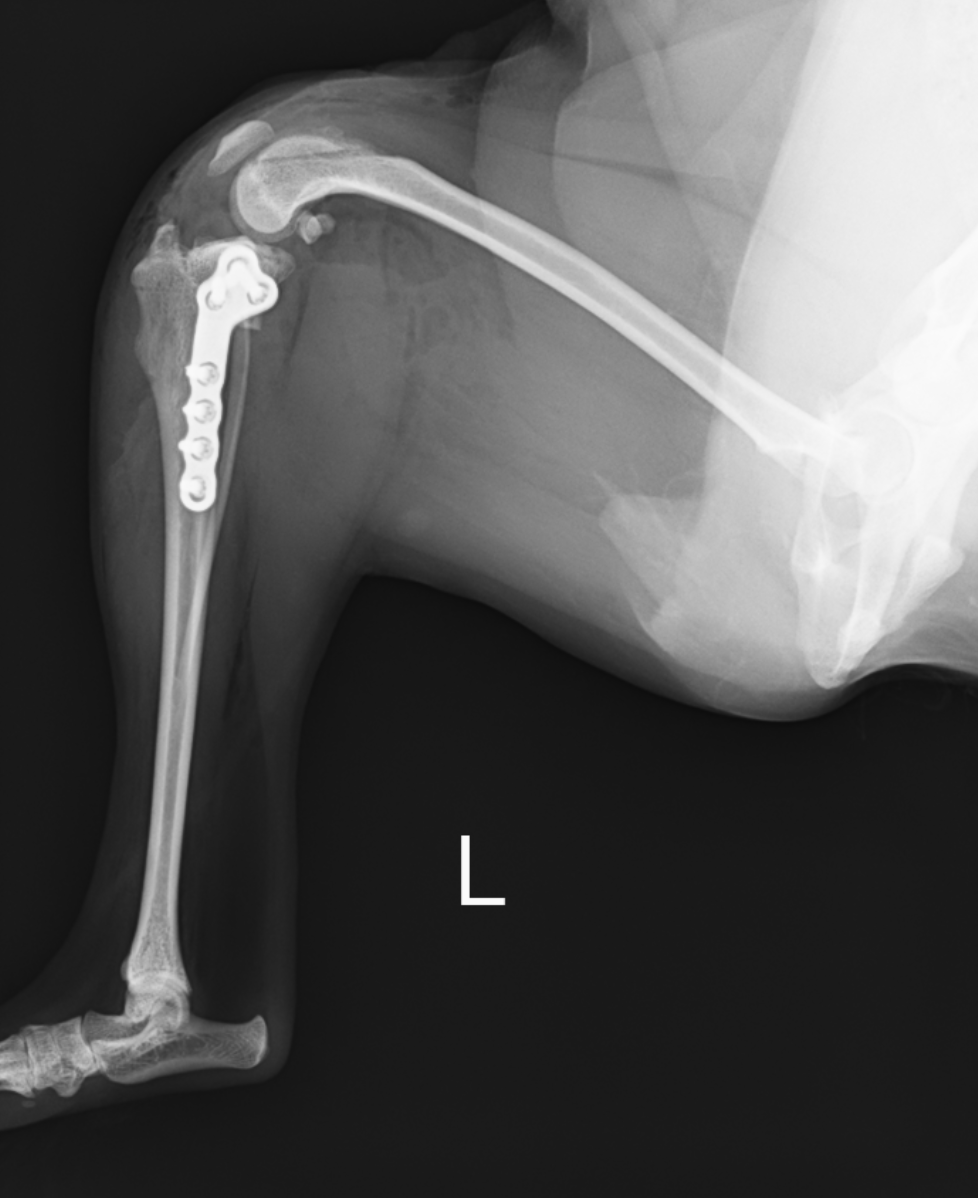

治療には特殊なTPLOソーという丸い鋸で骨を切断して回転させ、TPAを5度に近づけることでCrTTをなくすTPLO法というものを行います。これにより、前十字靭帯がなくても歩行可能となります。最小で1kg代の子から、大きい子だと70kg代の子まで対応が可能です。

術後早いと次の日には歩くことが可能ですので、早期退院が望めます。手術の痛みはあるので、数日の入院をおすすめはしていますが、入院が難しいこの場合には早期退院をするケースもあります。